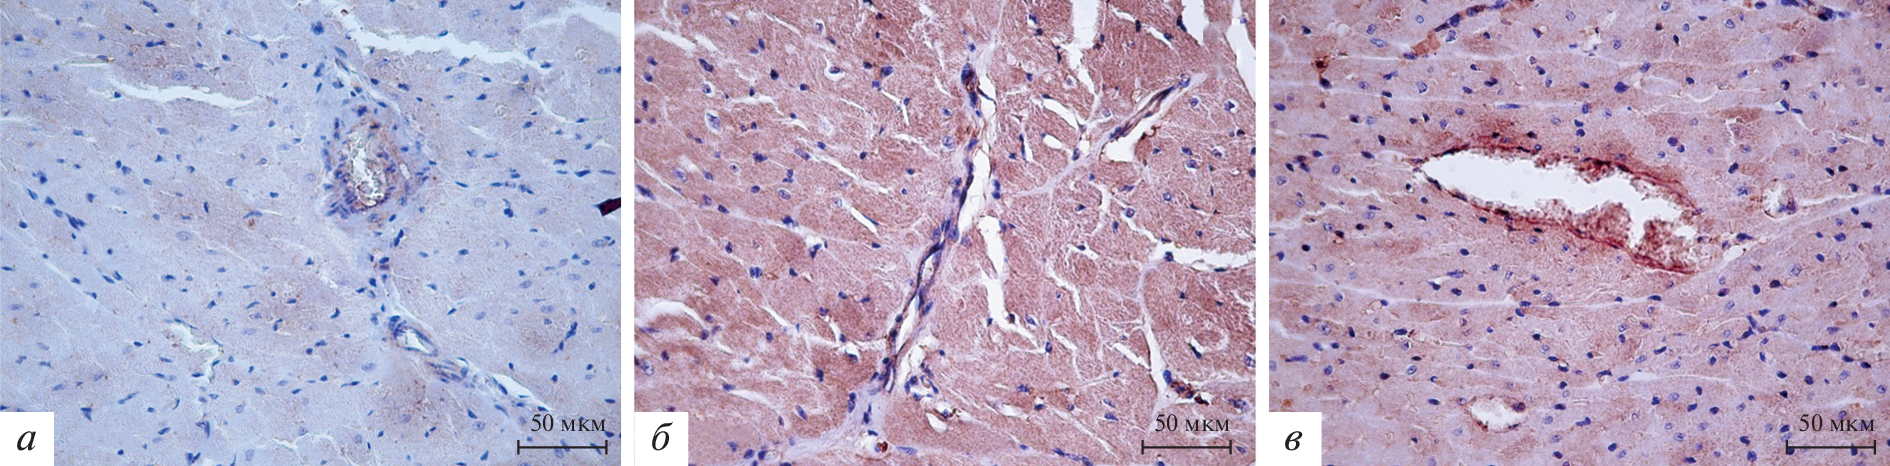

Immunohistochemical detection of matrix metalloproteinases (MMP) 2 and 9 was carried out in the myocardium of the left ventricle of prematurely born (21 and 21.5 days of gestation) and full-term (22 days of gestation) rats at 42, 56 and 180 days of the postnatal period of ontogenesis. The intensity of immunopositive staining was assessed by a scoring system. Preterm birth leads to an increase in the intensity of the immunopositive reaction to MMP-2 and MMP-9 in the wall of the left ventricle of rats. An increase in the intensity of the MMP-2 positive reaction in the left ventricle of rats is observed the earlier, the greater the degree of prematurity. The intensity of the MMP-9 positive reaction in the left ventricle of male rats is greater with a more pronounced degree of prematurity. An increase in the intensity of the MMP-2 and MMP-9 positive reaction in the wall of the left ventricle of female rats due to preterm birth is determined exclusively in animals born on the 21st day of pregnancy, that is, with a greater degree of prematurity.